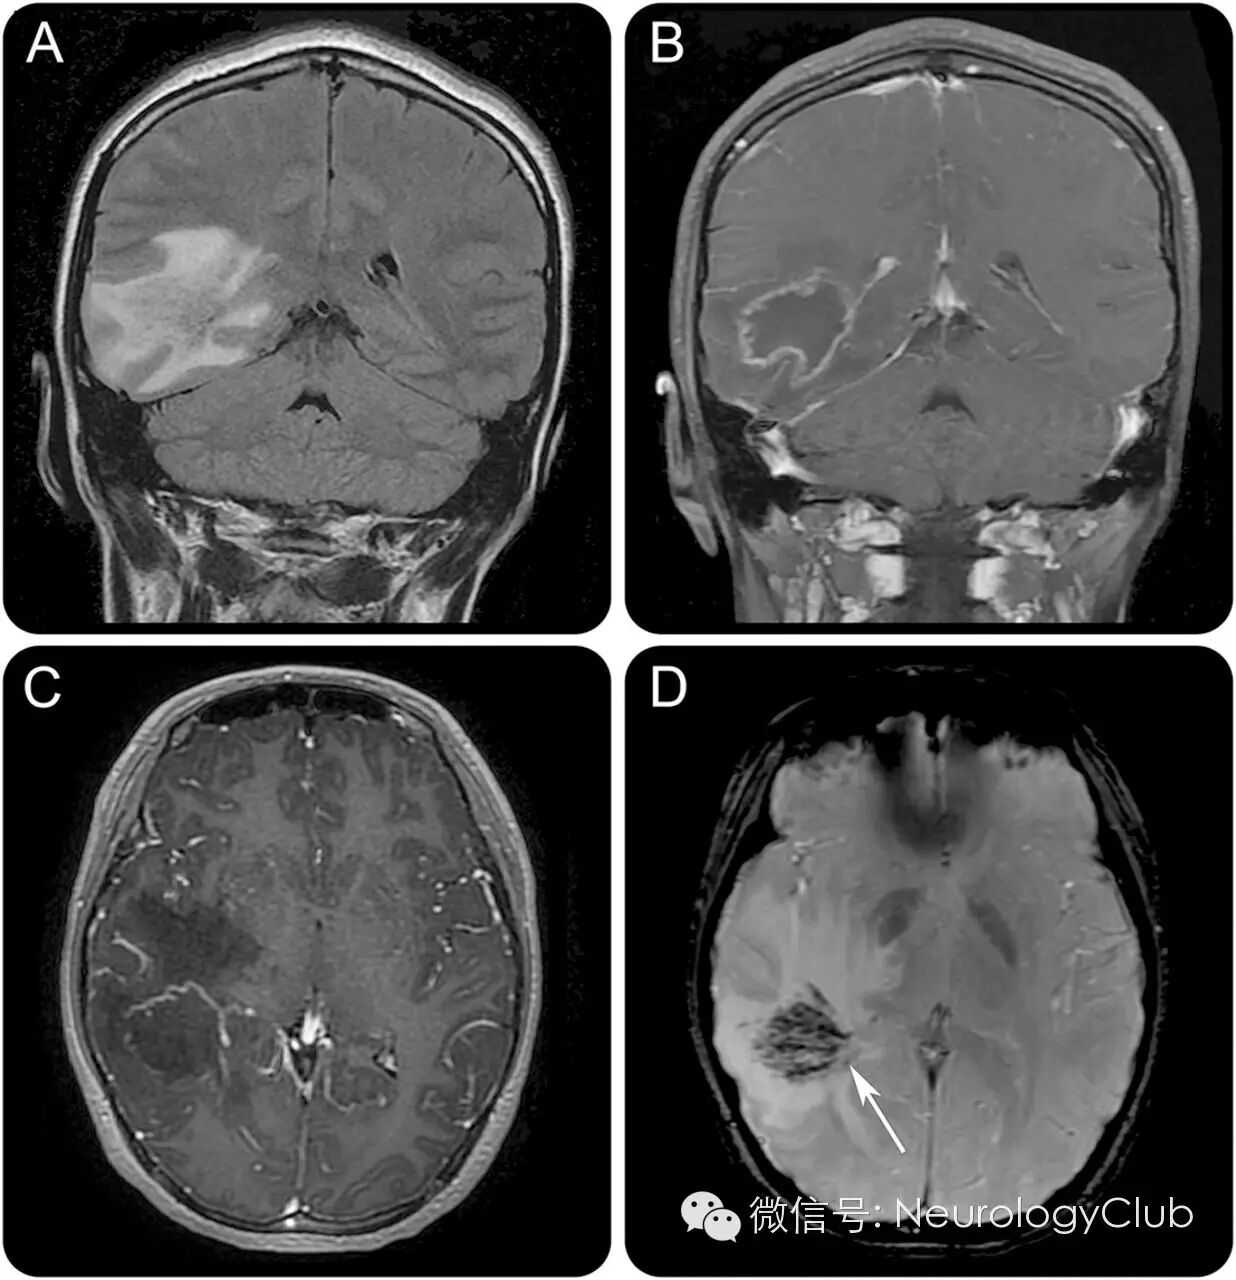

(图2:另一例原发性中枢神经系统血管炎的影像学表现。A:FLAIR;B-C:T1+C;D:T2*上位于中心的分支引流静脉符合充盈/血栓形成的小静脉/小静脉炎,是识别血管性病因并与肿瘤鉴别的关键)

中枢神经系统血管炎可表现为颅内肿瘤样病灶。T2* MRI可见静脉分支是其与脑肿瘤鉴别的关键(图1 D,图2 D)。